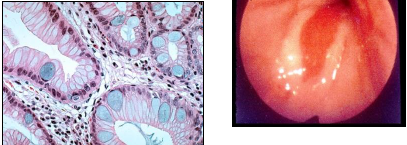

Pathology? (intestines; left normal)

celiac